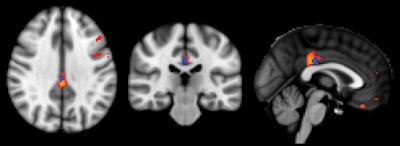

ASL-MRI showed decreased relative cerebral blood flow in the posterior cingulate cortex in subjects with deteriorated cognitive function versus those with stable cognitive function. Image courtesy of Radiology.Regarding the performance of ASL-MRI, the scan "simply prolongs an already existing MRI investigation for a few minutes without irradiation or contrast agent and is therefore minimally [disruptive] for the patients," Haller said. "Yet it provides complimentary information, which might help the early diagnosis of cognitive decline" and improve the identification of patients at risk, potentially leading to treatment that could slow or stop further decline.

Initial ASL-MRI scans showed decreased cerebral blood flow in the posterior cingulate cortex region of the brain in approximately half of the healthy subjects in the study, who later developed subtle cognitive decline.

At the 18-month follow-up, the researchers found that 75 subjects had remained stable. The remaining 73 had deteriorated cognitively and also showed reduced perfusion in their ASL-MRI exams at baseline, particularly in the posterior cingulate cortex.